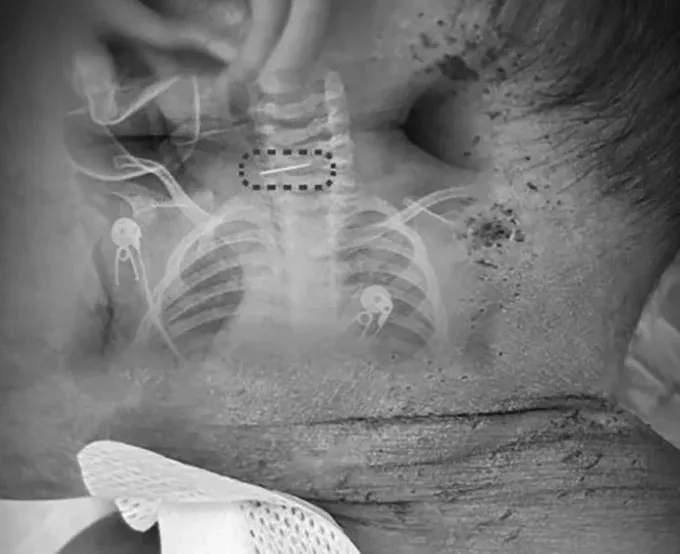

ก่อนหน้านี้ นายแพทย์ "สุย เหวิน หยวน" แพทย์จากศูนย์โรคกระดูกสันหลัง โรงพยาบาลซินหัว สังกัดมหาวิทยาลัยแพทยศาสตร์เจียวทง มหานครเซี่ยงไฮ้ ได้รับตัวเด็กเข้ารักษาในสภาพมีไข้สูง ผลการตรวจพบว่า "ตั้งแต่ศีรษะ ลำตัว ไปจนถึงแขนขา มีรอยเข็มแทงจำนวนประมาณ 500-600 แห่ง ซึ่งหลายจุดตกสะเก็ดสีดำแล้ว" และ "ที่น่าวิตกอย่างยิ่งคือ เราพบเข็มเย็บรองเท้าที่หักเป็น 2 ท่อน ฝังลึกอยู่บริเวณกระดูกสันหลังส่วนคอของเด็ก ซึ่งทางเราจึงต้องผ่าตัดฉุกเฉิน เพื่อนำสิ่งแปลกปลอมออก" และ "นี่เป็นการผ่าตัดที่มีความซับซ้อนอย่างยิ่ง เนื่องจากกระดูกสันหลังส่วนคอของทารกวัย 10 เดือนยังพัฒนาไม่สมบูรณ์ มีความเปราะบางสูง ความเสี่ยงจึงมากกว่าการผ่าตัดในผู้ใหญ่อย่างหลายเท่า!!" และ "เข็มเย็บพื้นรองเท้ามักมีเงี่ยงที่ปลาย หากดึงออกด้วยวิธีที่ไม่ถูกต้อง อาจเกี่ยวเนื้อเยื่ออ่อน และ ก่อให้เกิดการบาดเจ็บอย่างรุนแรง อีกทั้งปลายเข็มยังอยู่ใกล้หลอดเลือดแดง "คาโรติด" เพียงความผิดพลาดเล็กน้อย ก็อาจทำให้เด็กเสียชีวิตบนโต๊ะผ่าตัดได้ทันที!!"